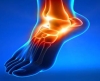

AYAKTA GUT HASTALIĞI Kanda ürik asit fazlalığı çağdaş toplumlarda çok kişinin sorunu olma yolundadır. Protein ağırlıklı beslenen ve obes olma sınırına yaklaşan bu kişilerde kandaki bu madde bir süre sonra eklemlere birikmeye başlar. İşte bu dönemde artık gut hastalığı başlamıştır.

Gut hastalığında kırmızı et ve mayalı içkileri bol bir ziyafetin sonrasında aniden gece yarısı başlayan şiddetli ayak başparmağı ağrısı ve şişmesi son derece tipiktir. Ağrı o denli şiddetlidir ki hastalar şimdiye kadar çektikleri en kötü ağrının bu olduğunu söylerler. Ortaçağda bu tip beslenme şansı sadece zenginlerde ve krallarda olduğu için bu hastalığa “kralların hastalığı“ adı verilmiştir. O zamanda yapılan tasvirlerde, gut krizi geçiren bu kişilerin ağrısının ne denli yüksek olduğunu göstermek için ayak başparmağını bir fare ısırıyor şeklinde resmedilirdi.

Hastalık sadece eklemlerde olmaz. Kulak kepçesinde bile ürik asit kristalleri birikebilmektedir. Zamanla özellikle ellerde öyle ciddi deformasyonlar oluşabilir ki kişinin ellerini kullanması imkansız hale gelebilir.